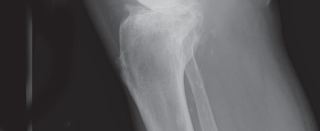

High-quality, standardized, weight-bearing radiographs are the cornerstone of preoperative planning. A standard knee series must include a weight-bearing anteroposterior (AP) view, a weight-bearing lateral view in extension, and a skyline (Merchant) view of the patella. The AP view reveals joint space narrowing, subchondral sclerosis, osteophyte formation, and the presence of subchondral cysts. The lateral view is essential for assessing patellar height (Insall-Salvati ratio) and the posterior slope of the tibia.

Crucially, we must obtain a 45-degree posteroanterior (PA) weight-bearing view (the Rosenberg view). Because cartilage wear in early-to-moderate OA predominantly affects the posterior aspect of the femoral condyles, the standard extension AP view may falsely appear normal. The flexed Rosenberg view unloads the patella and brings the worn posterior condyles into contact with the tibia, revealing hidden joint space narrowing. Furthermore, a full-length, hip-to-ankle standing radiograph is highly recommended, particularly in patients with severe deformities or a history of prior femoral/tibial fractures, to accurately determine the mechanical axis and identify any extra-articular deformities that might complicate intramedullary instrumentation.